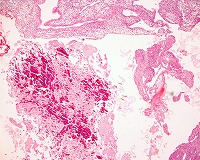

| 症例ー3 | |||

材料:子宮内膜 |

年齢:44歳、女性 |

●子宮膣部びらん、子宮体癌の疑い |

| HE | HE | HE | HE |

●組織診断:Undifferentiated carcinoma with endocrine differentiation |